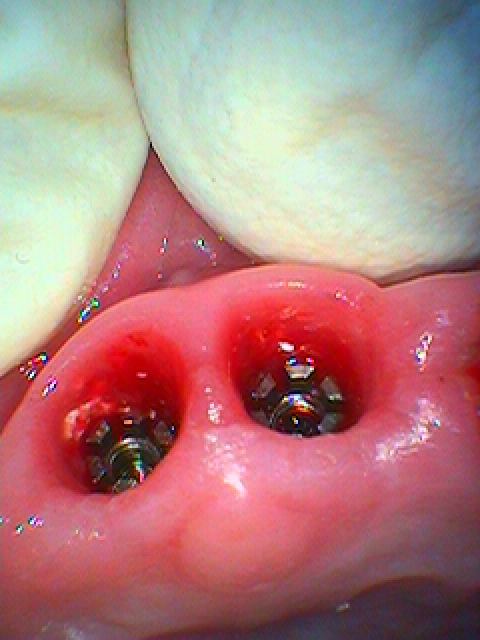

ブリッジが崩壊 歯根破折によりインプラント治療も余儀なくされた1症例|お知らせ |広島市安佐南区の歯科医院 ブリッジが崩壊 歯根破折によりインプラント治療も余儀なくされた1症例 トップ お知らせ・ブログ お知らせ ブリッジが崩壊 歯根破折によりインプラント治療も余儀なくされた1症例 ブリッジが崩壊 歯根破折によりインプラント治療も余儀なくされた1症例 3か月仮歯にて傷を待ちました 仮歯を外した状態になります 口腔内になります インプラント部の傷も癒えました インプラント部の埋入深さになります 切歯菅もあるため少し傾斜します アバットメントの印象時になります Web診療予約 初めての方へ 選ばれ続ける理由 院内設備について 歯が痛いしみる一般歯科 歯がぐらぐらする歯周病 健康な歯を保ちたい予防歯科 子供の虫歯予防をしたい小児歯科 銀歯をセラミックに審美歯科 白い歯を目指しませんか?ホワイトニング 矯正専門医がいるので安心矯正歯科 抜けた歯を補いたいインプラント・入れ歯 医院案内 スタッフ紹介 メリィハウス歯科クリニックオフィシャルホームページ ラベンダー歯科クリニックオフィシャルホームページ お知らせ・ブログ ホーム 診療科目 一般歯科 歯周病治療 予防治療 小児歯科 審美治療 ホワイトニング 矯正歯科 入れ歯・インプラント マウスピース矯正 初めての方へ 院長・スタッフ 設備紹介 医院案内・アクセス メニューを閉じる